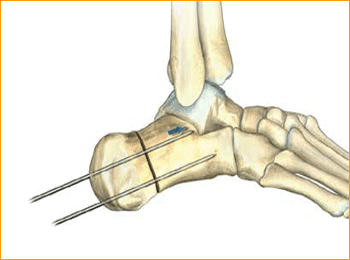

Jones Fracture Technique for 4.5 mm and 5.5 mm Headless Compression screws.

2. INDICATION AREA OUTLINE

The base of the fifth metatarsal is outlined, including the insertions of the peroneus brevis and tertius tendons.

3. APPROACH AND EXPOSURE

The guide wire, .062″, for the 4.7 Screw can be positioned at the base of the fifth metatarsal under fluoroscopic guidance. A small incision is made at the base of the fifth metatarsal at the intersection of the peroneus brevis and tertius tendons. Care is made to identify and protect the sural nerve branches which run over the peroneal tendons. If necessary, fibers of the lateral aponeurosis and peroneus brevis tendon are separated and retracted away from the styloid process of the base of the fifth metatarsal. A mini Hohman Retractor is placed on the plantar

aspect of the base of the fifth metatarsal. The surgeon’s fingers can be used to reduce the fifth metatarsal fracture by placing them in between the fourth and fifth metatarsals. This closes down the fifth metatarsal fracture site during guide wire, drill, and screw placement. A guide wire is drilled from the base of the fifth metatarsal into the central portion of the metatarsal shaft. It is maintained within the intramedullary canal in order to avoid distal penetration. Confirm placement with fluoroscopy.

4. MEASURE DEPTH

Depth is measured from the exposed portion of the guide wire with the cannulated depth gauge.

5. ADVANCE GUIDE WIRE

After selecting the size, advance the guide wire approximately 5 mm to maintain distal pin fixation before drilling.

Caution: Make sure not to compromise distal joint surfaces when advancing the guide wire.

6. SOFT TISSUE GUIDE PLACEMENT

Place the soft tissue guide (the guide should be used throughout) over the guide wire and open the near cortex using the appropriate cannulated profile drill.

7. DRILL

Leaving the soft tissue guide in place, drill into the far fragment with the appropriate cannulated, long drill. Reference the markings on the drill to confirm desired depth.

Tip: The long drill is recommended to mitigate the effects of varying bone density and distraction upon screw insertion.

8. FRACTURE COMPRESSION

In order to account for countersinking and fracture compression, a screw that measures 5 mm shorter than the measured total depth is inserted over the guide wire while protecting the soft tissues with a soft tissue guide.

9. SCREW INSERTION

The screw is placed while under fluoroscopic guidance in order to avoid cortical penetration. Postoperative protocol: The patient is placed into a soft dressing, supported by a fiberglass splint. Patients can be made non-weight-bearing for a period of 2–6 weeks postoperatively depending upon Torg type of fracture, bone quality, and underlying morbidities.